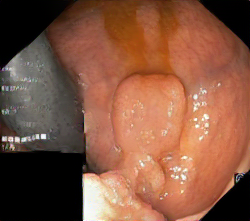

We have used a polyp dataset published with HyperKvasir dataset [51], which consists of polyp findings extracted from endoscopy examinations. HyperKvasir contains polyp images with corresponding segmentation masks annotated by medical experts. We use only this polyp dataset as a case study because of the time and resource-consuming training process of the SinGAN-Seg pipeline. However, the SinGAN-Seg model and pipeline can be used for any segmentation dataset.

A few sample images and the corresponding masks of the polyp dataset in HyperKvasir are shown in Fig 2. The polyp images are RGB images. The masks of the polyp images are single-channel images with white () for true pixels, which represent polyp regions, and black () for false pixels, which represent clean colon or background regions. In this dataset, there are different sizes of polyps. The distribution of polyp sizes as a percentage of the full image size is presented in the histogram plot in Fig 3, and we can observe that there are more relatively small polyps compared to larger polyps. Additionally, a subset of this dataset was used to prove that the performance of segmentation models trained with small datasets can be improved using our SinGAN-Seg pipeline, and the whole dataset was used to show the effect of using SinGAN-Seg generated synthetic images instead of a large dataset which has enough data to train segmentation models. In this regard, this dataset was used for two purposes: